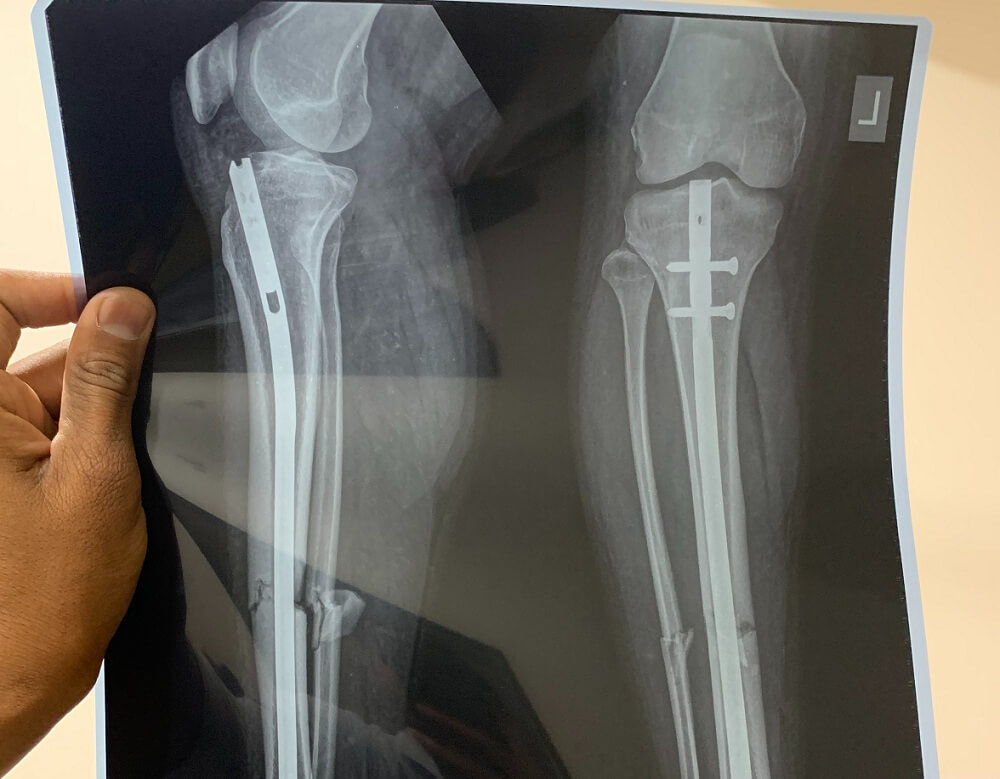

Травматолог – это врач, который консервативным или оперативным методом лечит повреждения костной ткани, помогает в реабилитации и восстановлении после операций на опорно-двигательной системе.